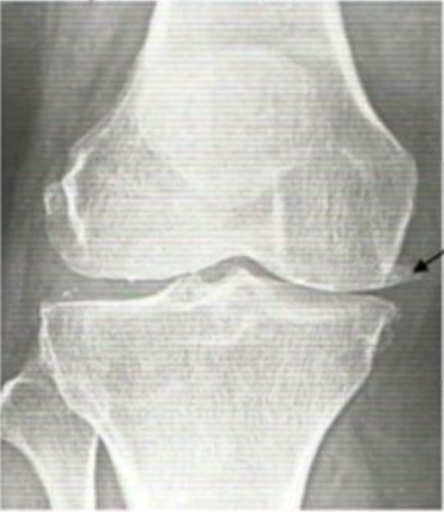

Eat this 'candy' for new knees

Published: Fri, 12/03/21